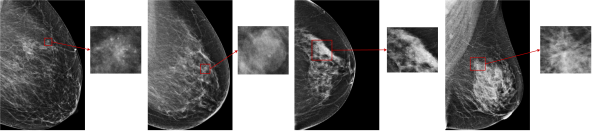

Screening mammography is inherently different from typical natural images from a few perspectives. First of all, as illustrated in Figure 1, regions of interest (ROI) in mammography images, such as masses, asymmetries, and microcalcifications, are often smaller in comparison to the salient objects in natural images. Moreover, as suggested in multiple clinical studies [72, 53, 73], both the local details, such as lesion shape, and global structure, such as overall breast fibroglandular tissue density and pattern, are essential for accurate diagnosis. For instance, while microcalcifications are common in both benign and malignant findings, their presence in a ductal distribution, such as in the third example of Figure 1, is a strong indicator of malignancy. This is in contrast to typical natural images where objects outside the most salient regions provide little information towards predicting the label of the image. In addition, mammography images are usually of much higher resolutions than typical natural images. The most accurate deep CNN architectures for natural images are not applicable to mammography images due to the limited size of GPU memory.

In Figure 7, we visualize saliency maps for four samples selected from the test set. In the first two examples, the saliency maps are highly activated on the annotated lesions, suggesting that our model is able to detect suspicious lesions without pixel-level supervision. Moreover, the attention is highly concentrated on ROI patches that overlap with the annotated lesions. In the third example, the saliency map for benign findings identifies three abnormalities. Although only the top abnormality was escalated for biopsy and hence annotated by radiologists, the radiologist’s report confirms that the two non-biopsied findings have a high probability of benignity and a low probability of malignancy. In the fourth example, we illustrate a case when there is some level of disagreement between our model and the annotation in the dataset. The malignancy saliency map only highlights part of a large malignant lesion with segmental coarse heterogeneous calcifications. This behavior is related to the design of : a fixed pooling threshold cannot be optimal for all sizes of ROI. The impact of is further studied in 3.6. This example also illustrates that while human experts are asked to annotate the entire lesion, CNNs tend to emphasize only the most informative regions. While no benign lesion is present, the benign saliency map still highlights regions similar to that in the malignancy saliency map, but with a lower probability than the malignancy saliency map. In fact, calcifications with this morphology and distribution can also result from benign pathophysiology [42].